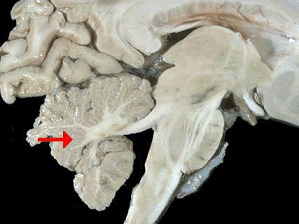

如图箭头所示为大脑哪个部位()

A.顶叶

B.枕叶

C.小脑

D.脑干

E.额叶